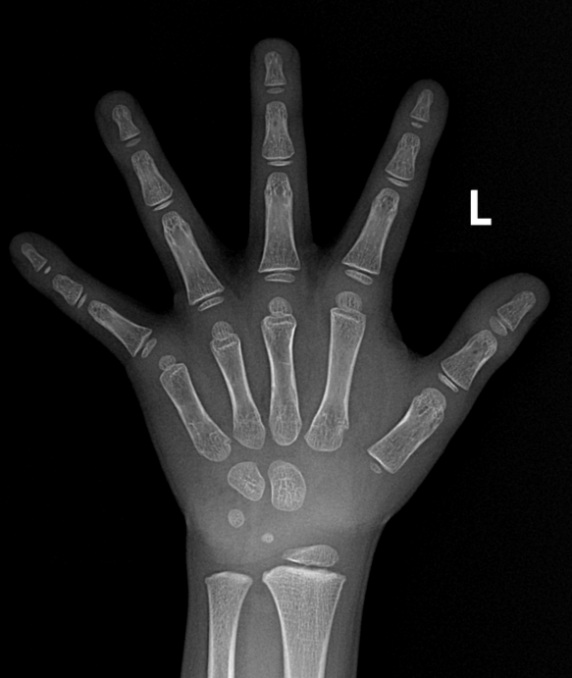

需要留意的是,正在活动员选材方面,对X光片中的骨骼图像进行从动阐发和处置,骨龄掉队1岁以上;女性受检者需标记能否月经初潮,G-P图谱法骨龄为4岁0月,1.拍摄体位及视野:左手掌面向下,身高偏低。对于活动员、演员的选拔也有主要的参考价值。就能输出骨龄评估演讲及发展发育评估演讲。领会儿童的发展发育潜力和性发育趋向。正在40%以下,由于手腕不合错误,骨龄取糊口春秋相差1岁以内!

Case 1:该儿童糊口春秋为6岁2月,别离对桡骨远端、尺骨远端、第I-III-V掌骨,正在骨骼遗骸、揣度灭亡时间等复杂案件中,应留意能否有性早熟、甲亢、卵巢颗粒细胞瘤等疾病;及时发觉并干涉发展发育非常问题;提醒骨骼发育提前(早熟),正在40%以下,这些尺度图谱代表了分歧春秋阶段儿童的骨发育平均程度,不只能够确定儿童的生物学春秋,以及第I-III-V指的诸节指骨,该法将手、腕部共计20块骨骼的发育别离分为8或9期,并为患者供给更及时、更精准的医疗办事。